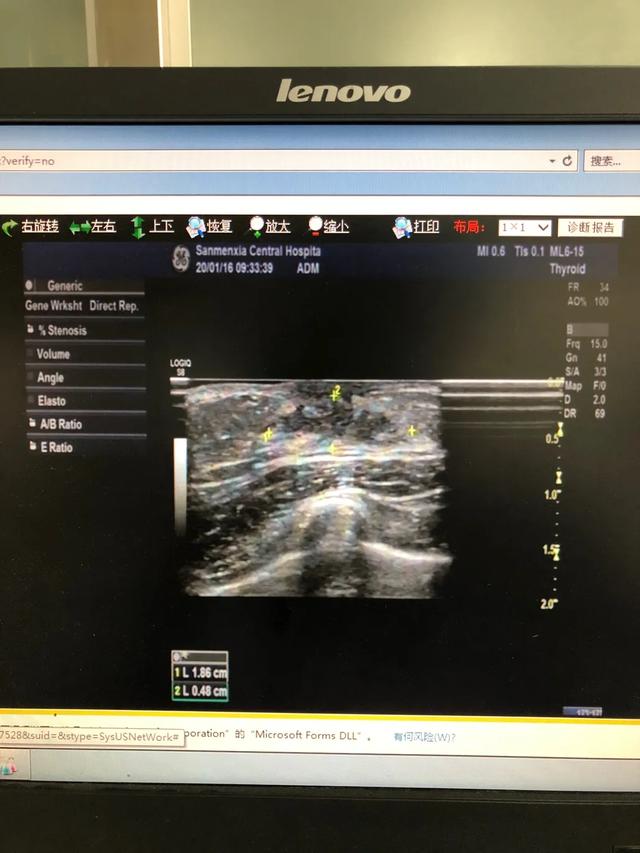

下图是一例患儿性早熟的B超结果、胸片结果及血清学化验结果。

从检查结果来看,B超显示子宫卵巢有囊性回声;胸片显示乳腺发育;而血清学指标,促黄体生成素的峰值是13.09,促卵泡的峰值是20.91,LH/FSH=62.60%。